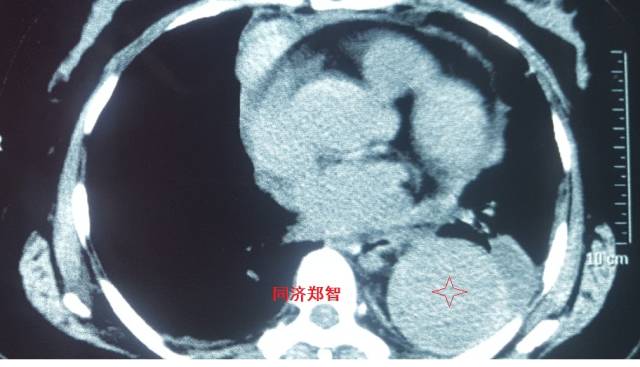

病例四

腹部平扫CT提示腹主动脉增宽,CTA证实为腹主动脉局限性夹层(红箭头所示)。